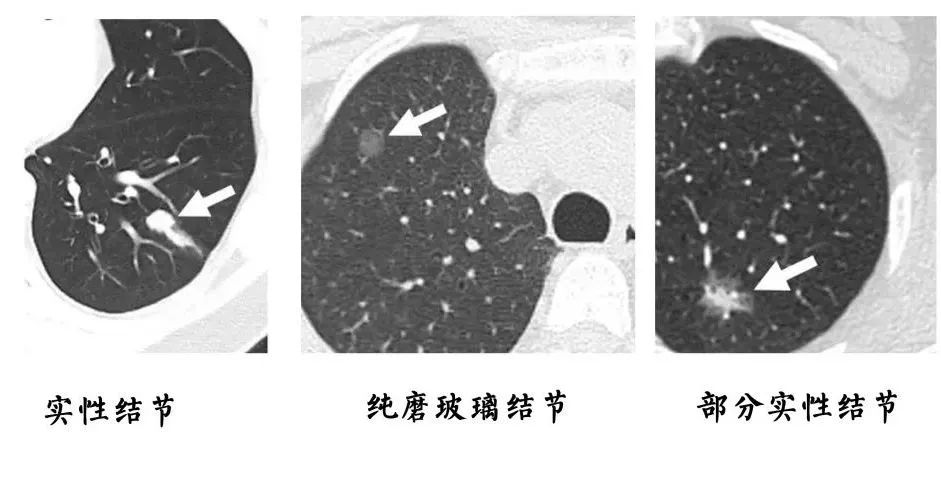

结节一般是指在CT、彩超、磁共振等检查中发现的直径小于3厘米的病灶。常见的有肺结节、乳腺结节和甲状腺结节。医生会根据结节的形状、密度、血液供应等特点,来初步判断这些结节的性质。虽然多数的结节为良性,但也有些结节是恶性肿瘤的前期表现,一旦检出,应该密切复查,及时干预治疗。